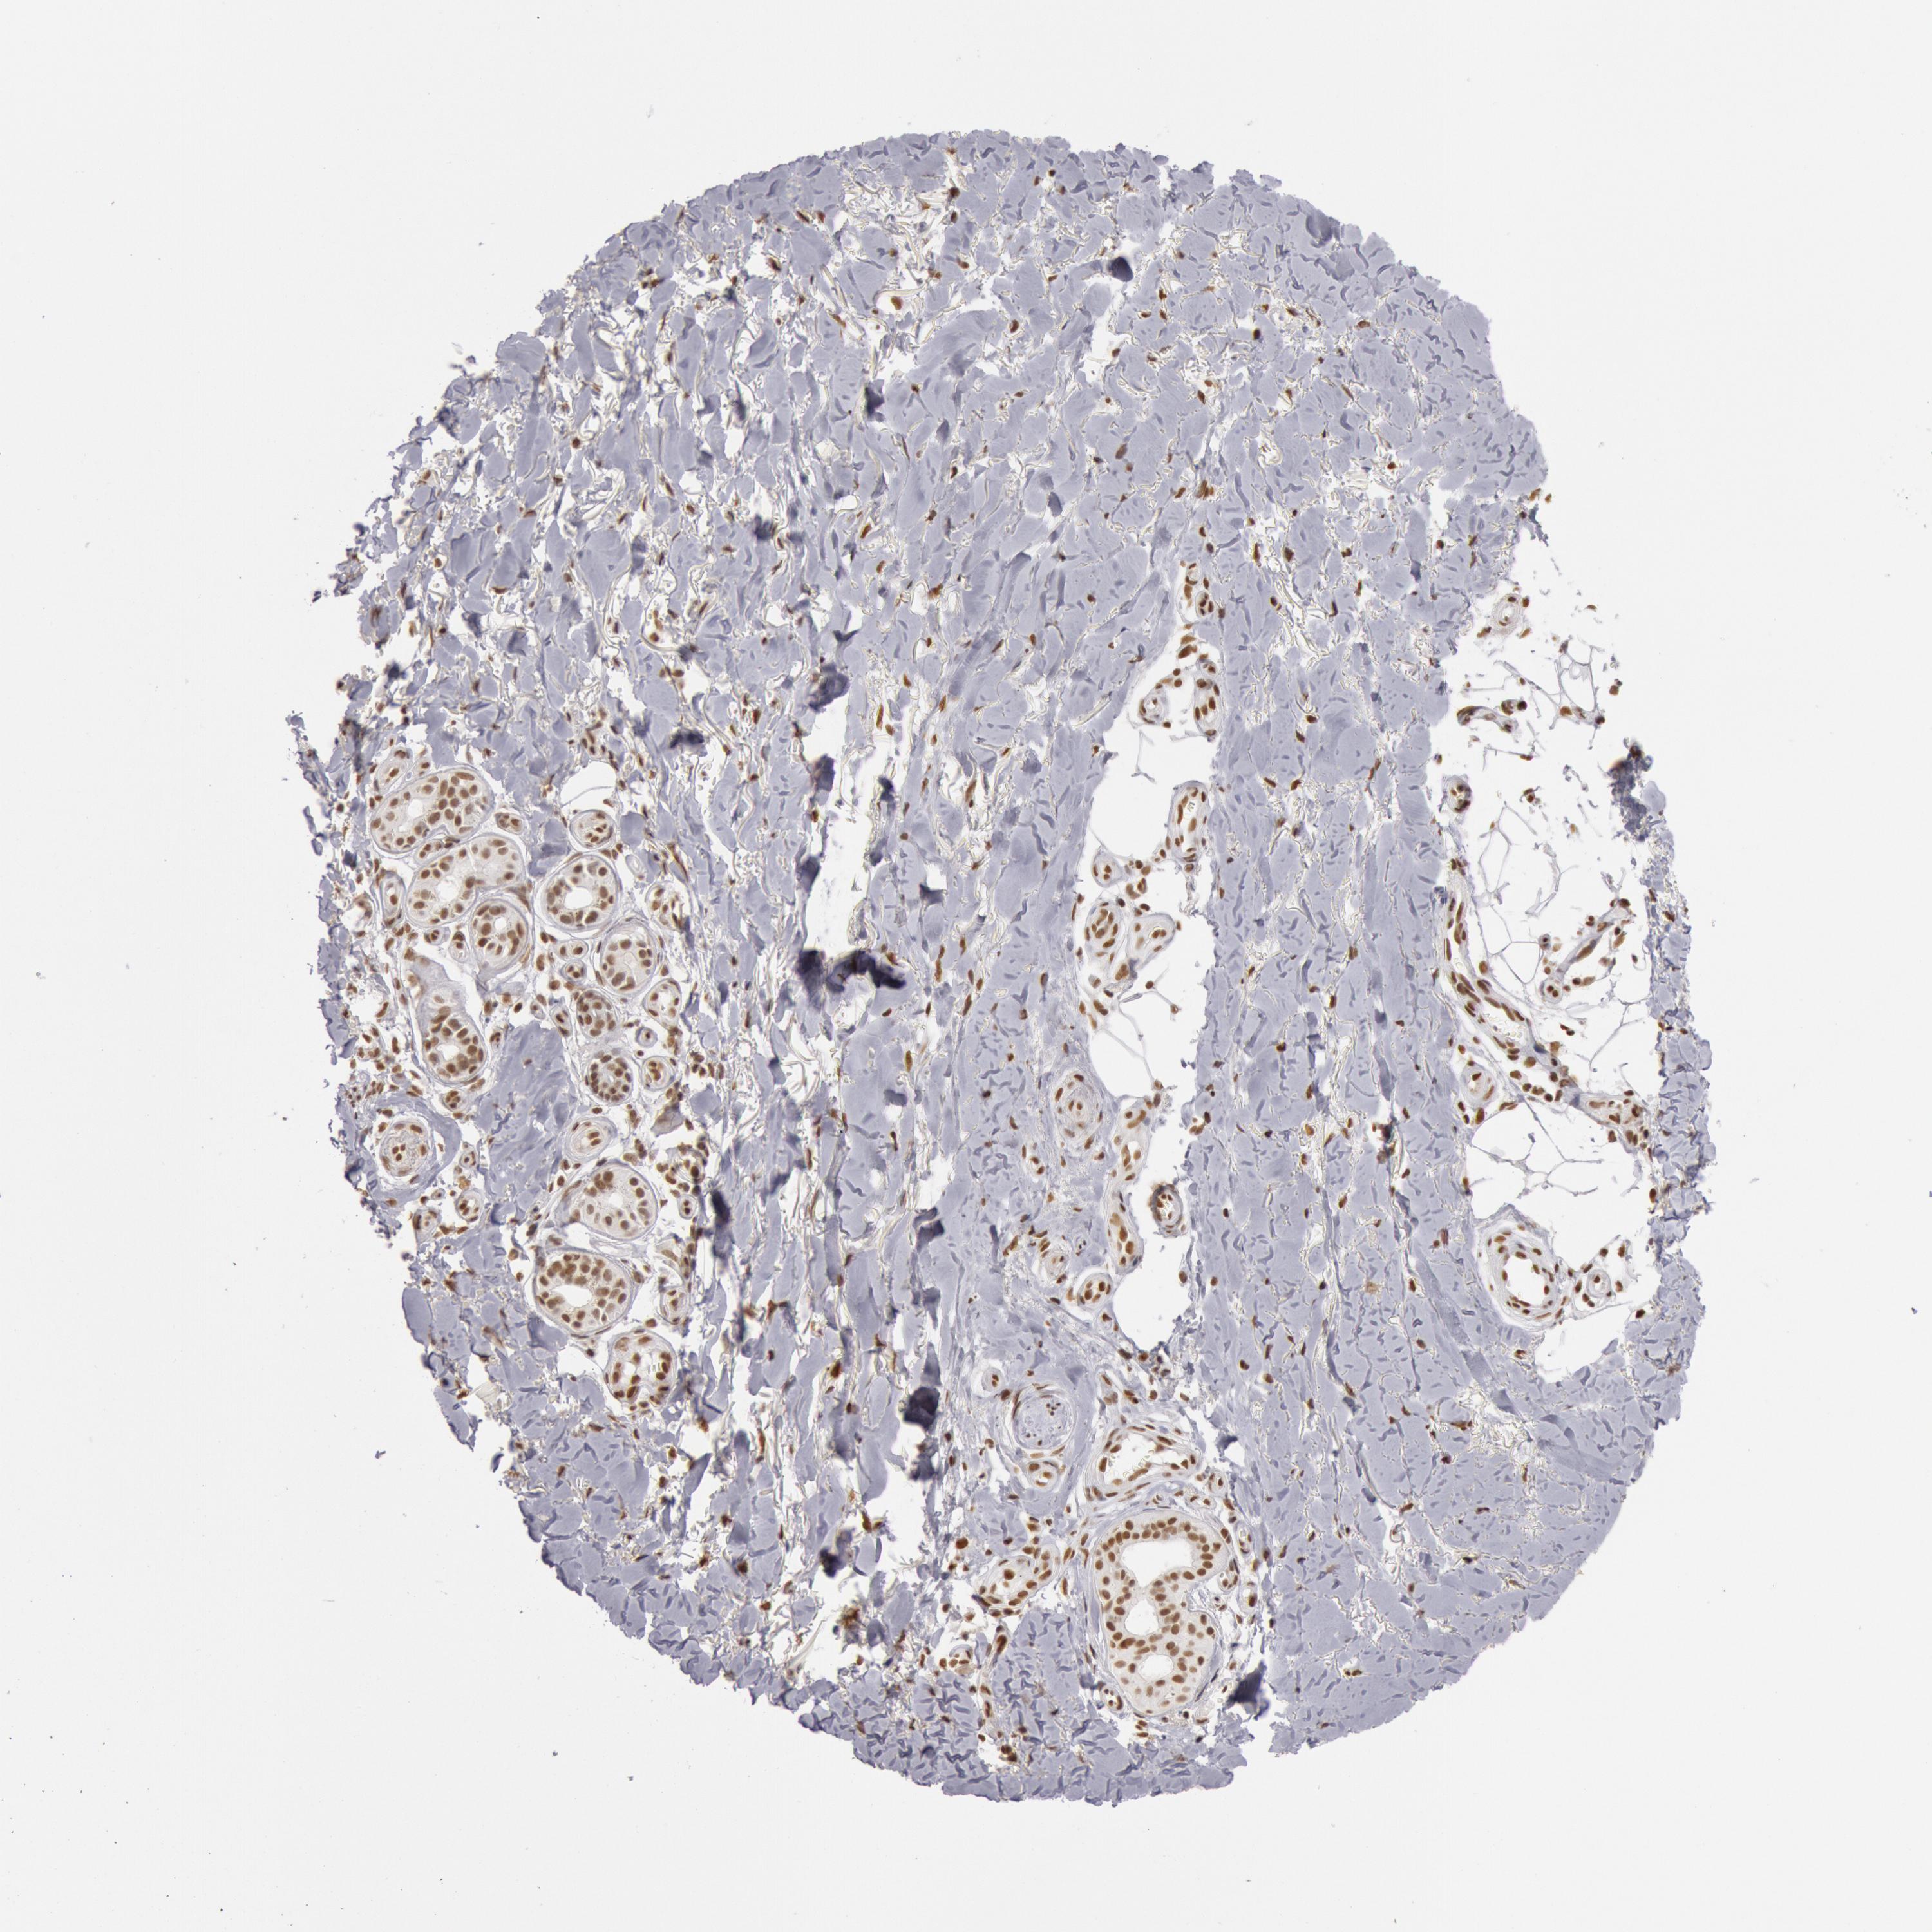

SKIN CANCER - Protein expressioni

A mouse-over function shows sample information and annotation data. Click on an image to view it in a full screen mode. Samples can be filtered based on level of antibody staining by selecting one or several of the following categories: high, medium, low and not detected. The assay and annotation is described here.

Antibody stainingi

Antibody staining in the annotated cell types in the current human tissue is reported as not detected, low, medium, or high, based on conventional immunohistochemistry profiling in selected tissues. This score is based on the combination of the staining intensity and fraction of stained cells.

Each image is clickable and will lead to virtual microscopy that enables deeper exploration of all samples and also displays staining intensity scores, fraction scores and subcellular localization as well as patient and tissue information for each sample.

Antibody HPA001221

Antibody HPA001222

Staining

High

Medium

Low

Not detected

Intensity

Strong

Moderate

Weak

Negative

Quantity

>75%

75%-25%

<25%

None

Location

Nuclear

Cytoplasmic/membranous

Cytoplasmic/membranous,nuclear

Squamous cell carcinoma, NOS

Basal cell carcinoma